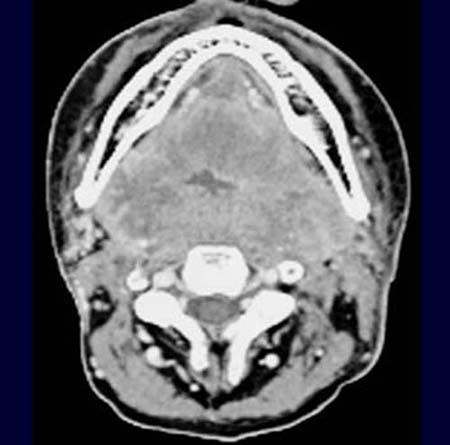

Patient mit Z.n. primärer Radio-Chemotherapie eines Plattenepithelkarzinoms

im Bereich des rechten Oropharynx.

Im

CT durch den Mundboden kommt nach Kontrastmittelgabe die gesamte Region als kontrastmittelaufnehmende

Raumforderung zur Darstellung. Eine eigentliches Lumen des Hypopharynx

ist nicht mehr abgrenzbar.